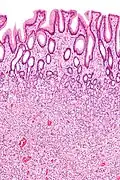

Tubular Adenoma (Villous, Tubulovillous) | Colorectal | Tubular glands with elongated nuclei (at least low-grade atypia) | Yes | ![]() |

|